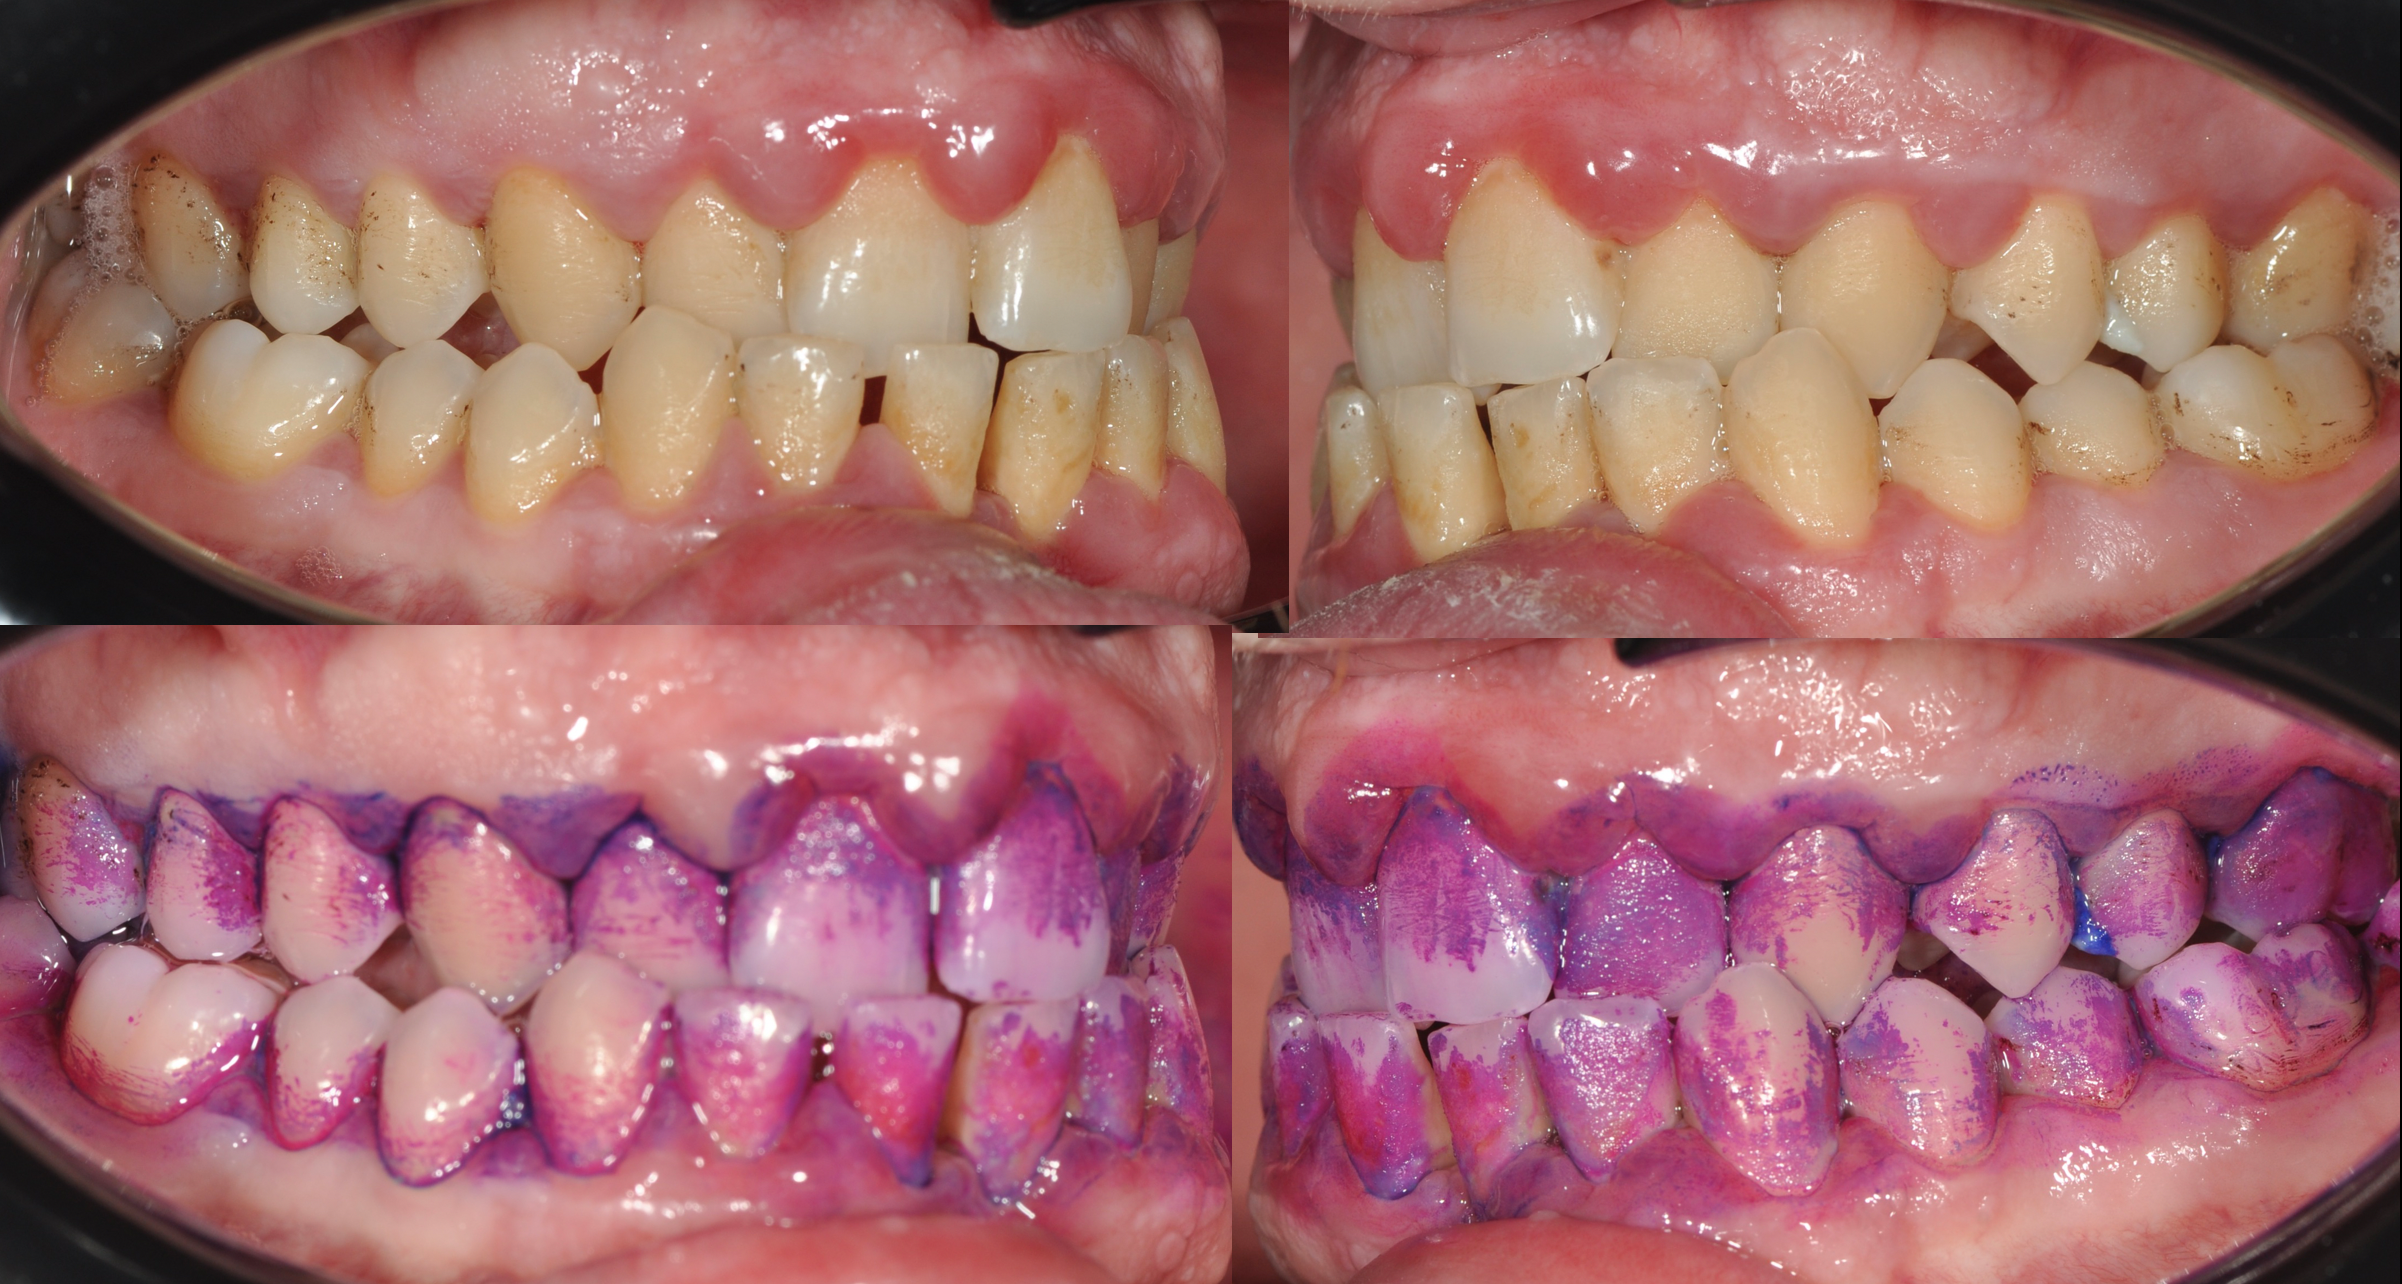

Le immagini cliniche del prima e dopo trattamento e il test di placca al 100% che accompagnano questo articolo mostrano visivamente quanto sia determinante il controllo del biofilm nella guarigione dei tessuti.

Un test di placca che evidenzia una copertura del 100%, come mostrato nell’immagine allegata, è un indicatore potentissimo della causa primaria della malattia: il biofilm batterico non controllato.

Il protocollo GBT – Guided Biofilm Therapy (foto in calce)

La fase di rivelazione del biofilm, come mostrato nell’immagine con test di placca al 100%, è fondamentale: rende il paziente consapevole del problema e trasforma la terapia in un percorso condiviso.

L’immagine del test di placca al 100% è particolarmente significativa: quando tutto è colorato, significa che il biofilm è ovunque. È da lì che bisogna partire.